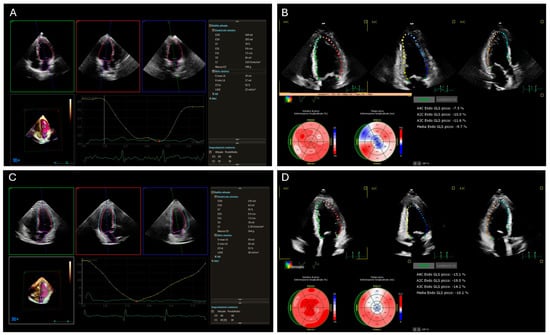

3. Echocardiography